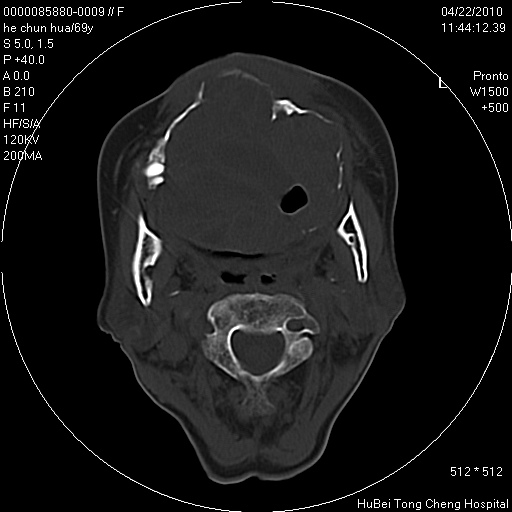

标题: CT25937:女,69Y

硬腭部包块十余年,渐进性增大。

不管以前,现在是恶性占位了

支持硬腭部恶性肿瘤!

硬腭部肿瘤恶变可能。

硬腭占位 恶性可能性大

考虑硬腭部肿瘤恶变可能。